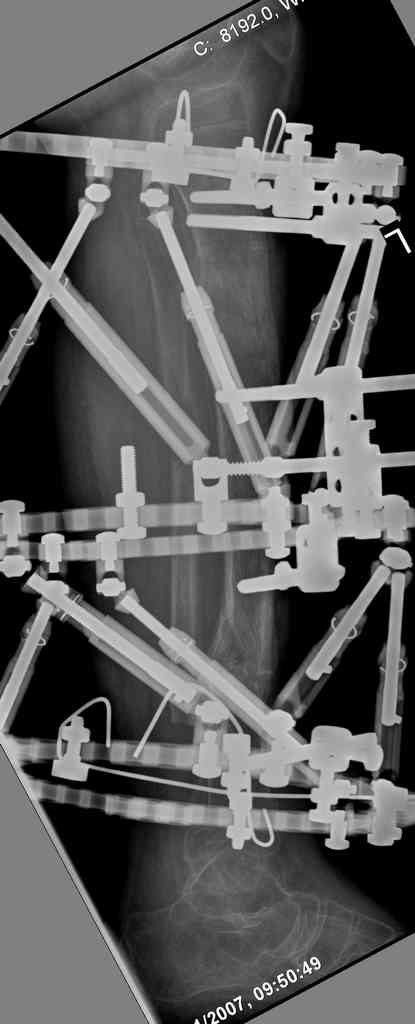

Another choice is simply perform shortening + posterior angulation with Ilizarov or TSF , than gradual correction of the angulation.After all apply third ring on the proximal tibia and start lengthening.

We had recently similar case in 14 years old boy with 45 mm bone defect after open tibial fracture.Boy doing excellent .This technique is not new, Sasha Lerner did it in Rambam , Rozbruch wrote also.

Another advantage of this techniqe is relaxation of soft tissue and possibility for closure even large defects of the skin.In your case I will apply ring on the foot and mid diaphysis of the tibia ,removal of the fibular plate,sindesmotic wire, and after correction of angulation on the proximal tibia.